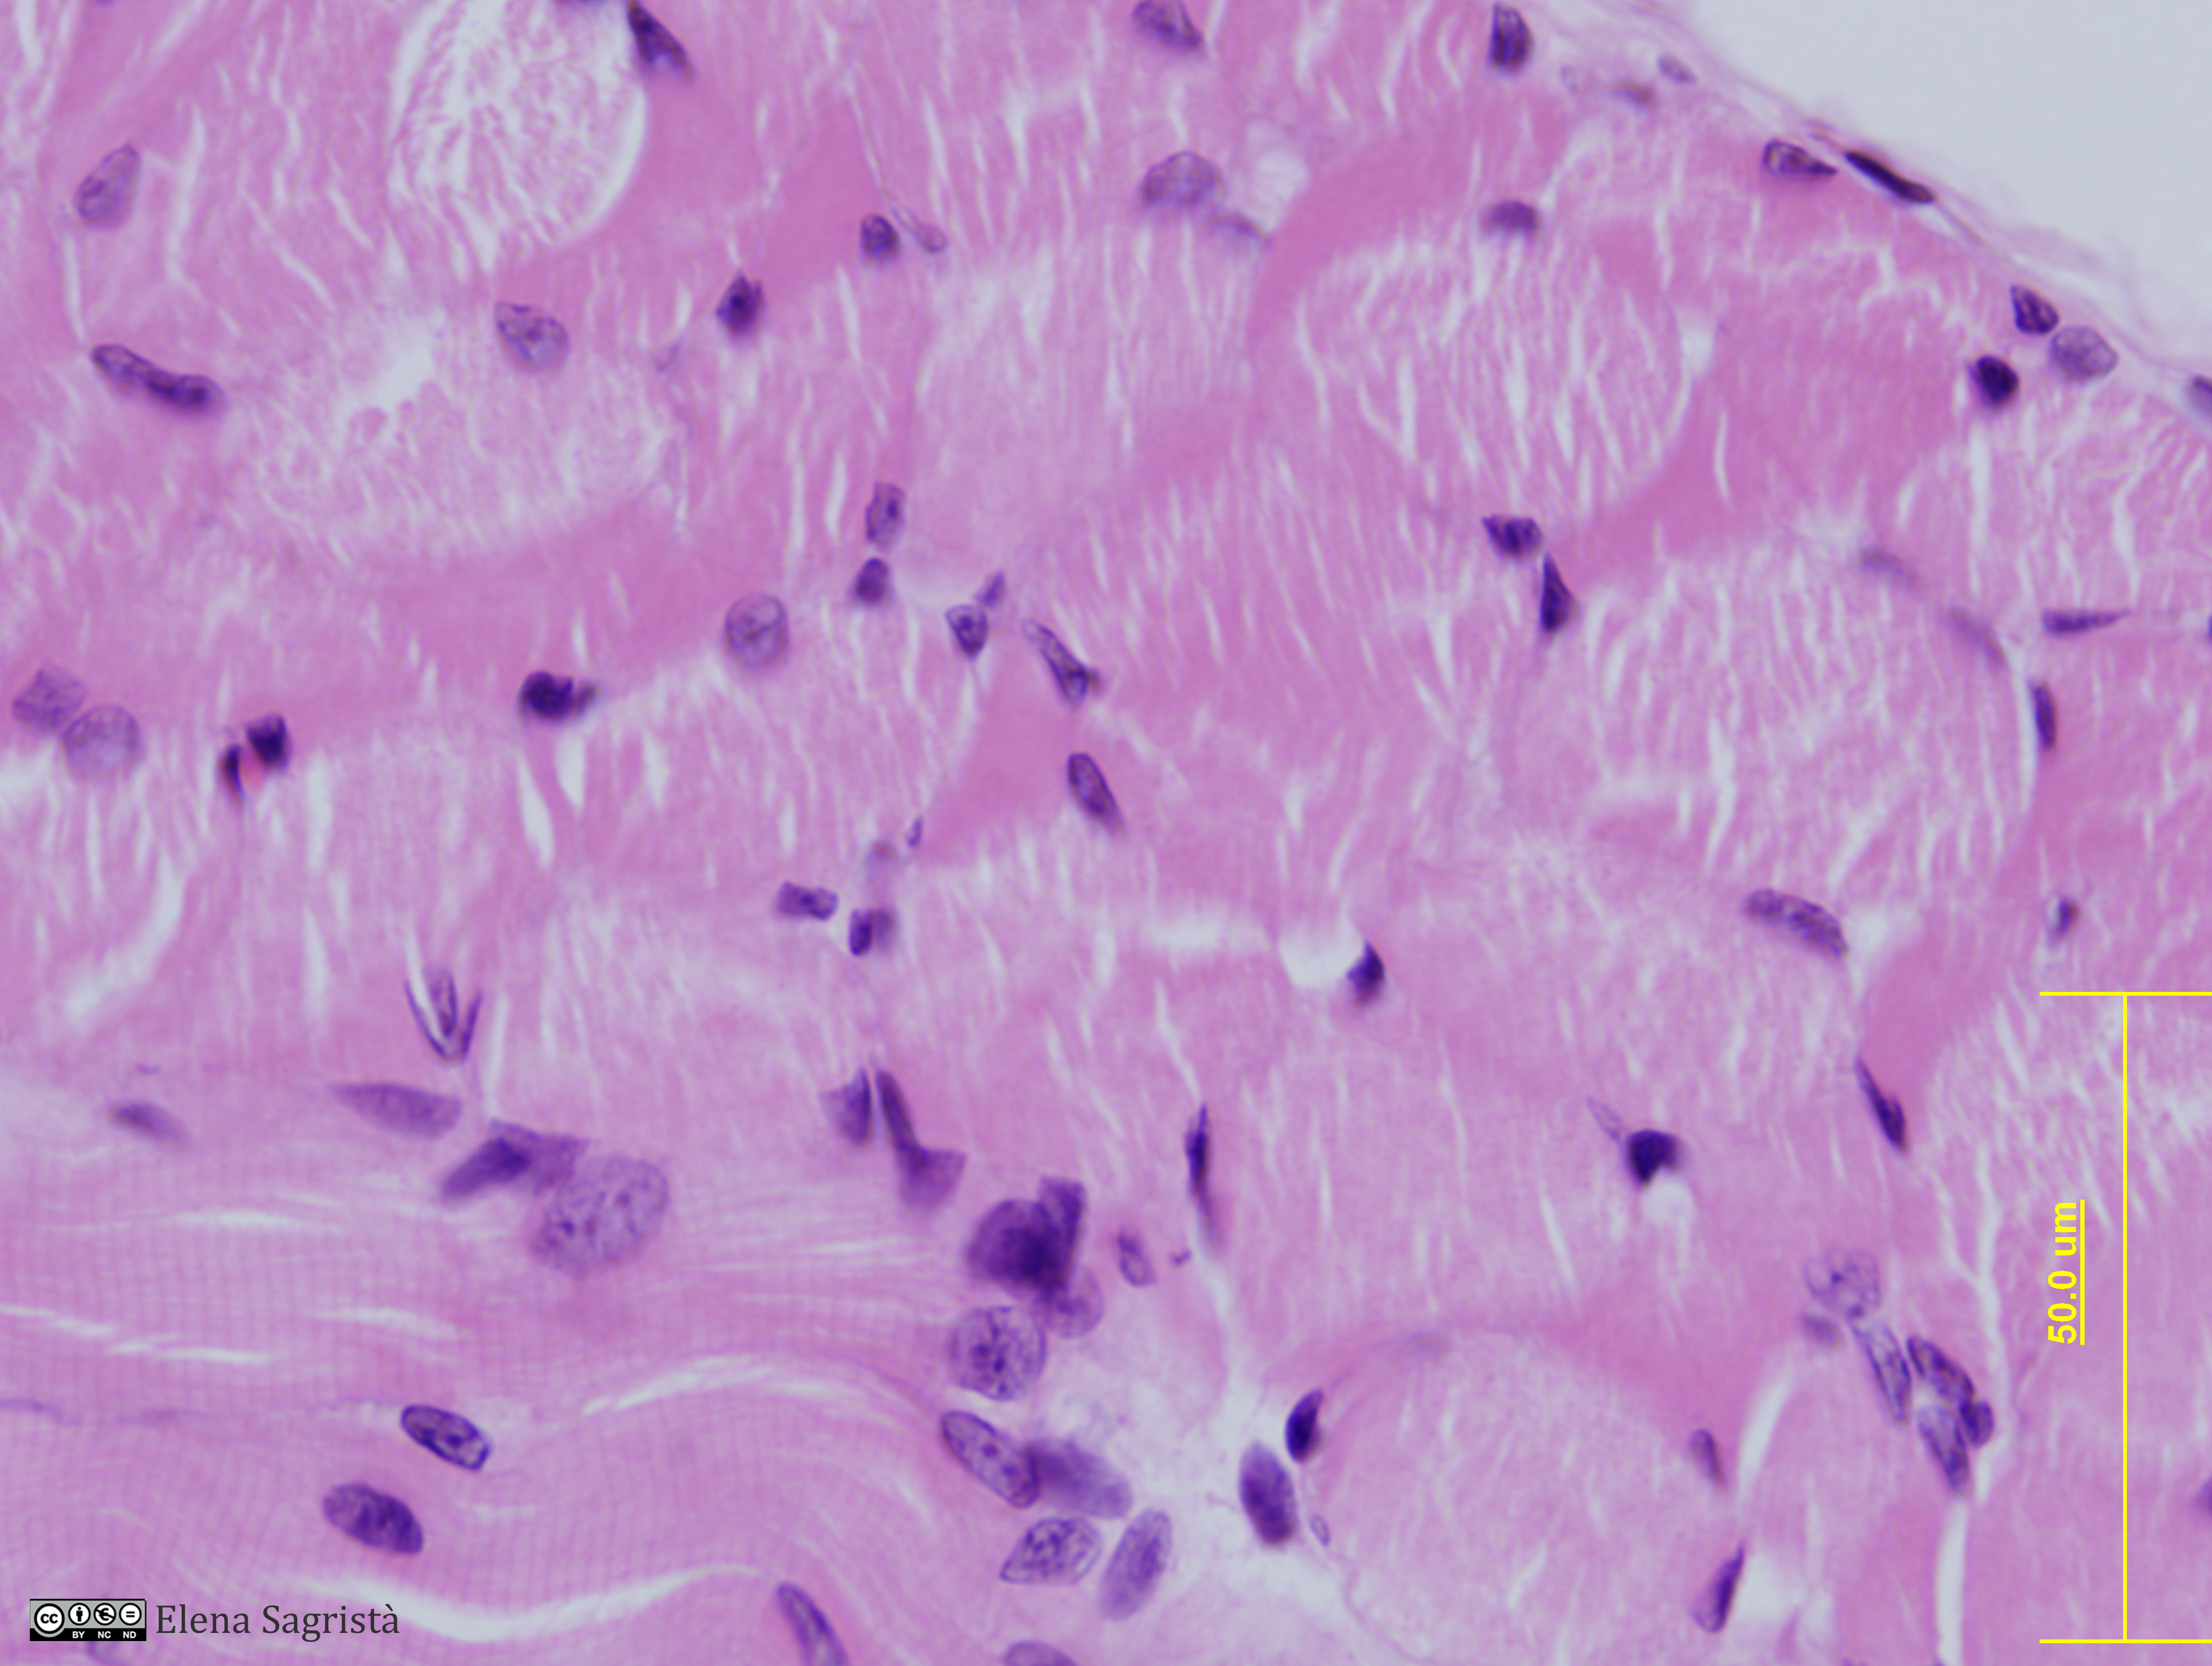

Histologia imatges: 07 Teixit muscular

Imatges de preparacions histològiques de Teixit muscular. Microscopia òptica.